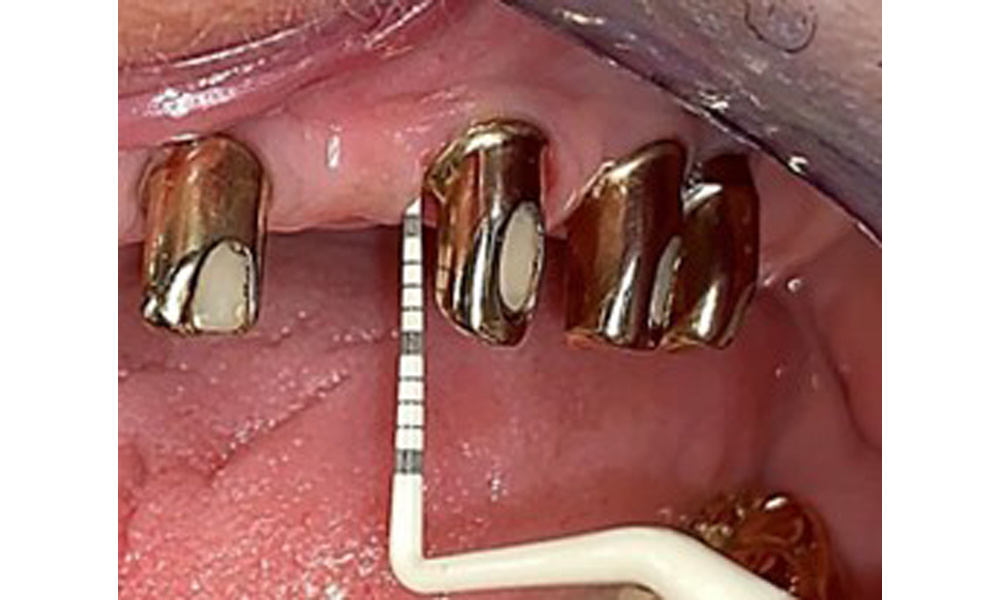

IPC cycle icon: magnifying glass

Based on the medical history, the risk of complications is classified as mild to moderate due to the intake of ASA 100 and bisoprolol. It should be noted that increased bleeding may occur during treatment, particularly if gingivitis is present. The risk is classified as low in the present case, as the patient maintains excellent intraoral hygiene. Due to the otherwise stable intraoral status over many years, the needs determined during the intraoral examination will be decisive for her treatment. The findings observed during any dental appointment will determine the subsequent course of treatment. Determination of bleeding status is mandatory to detect gingival changes in peri-implant tissues (Fig. 6).

Probing implant 23 at a probing depth of 4 mm using a plastic probe, showing negative BOP findings and a hyperplastic papilla.

Fig. 6: Probing implant 23 at a probing depth of 4 mm using a plastic probe, showing negative BOP findings and a hyperplastic papilla.

The periodontal status should be thoroughly examined once a year. This examination provides comprehensive documentation of the periodontal and implant findings, including pocket depths, periodontal recession and furcation involvement. This will ensure a rapid response to any potential progression of the mucositis, gingivitis, periodontitis or peri-implantitis. Implant probing using a plastic probe is recommended. In the present case, a mesial probing depth of 4 mm was detected mesial to implant 23. No suppuration or bleeding was detected, indicating the absence of peri-implantitis.